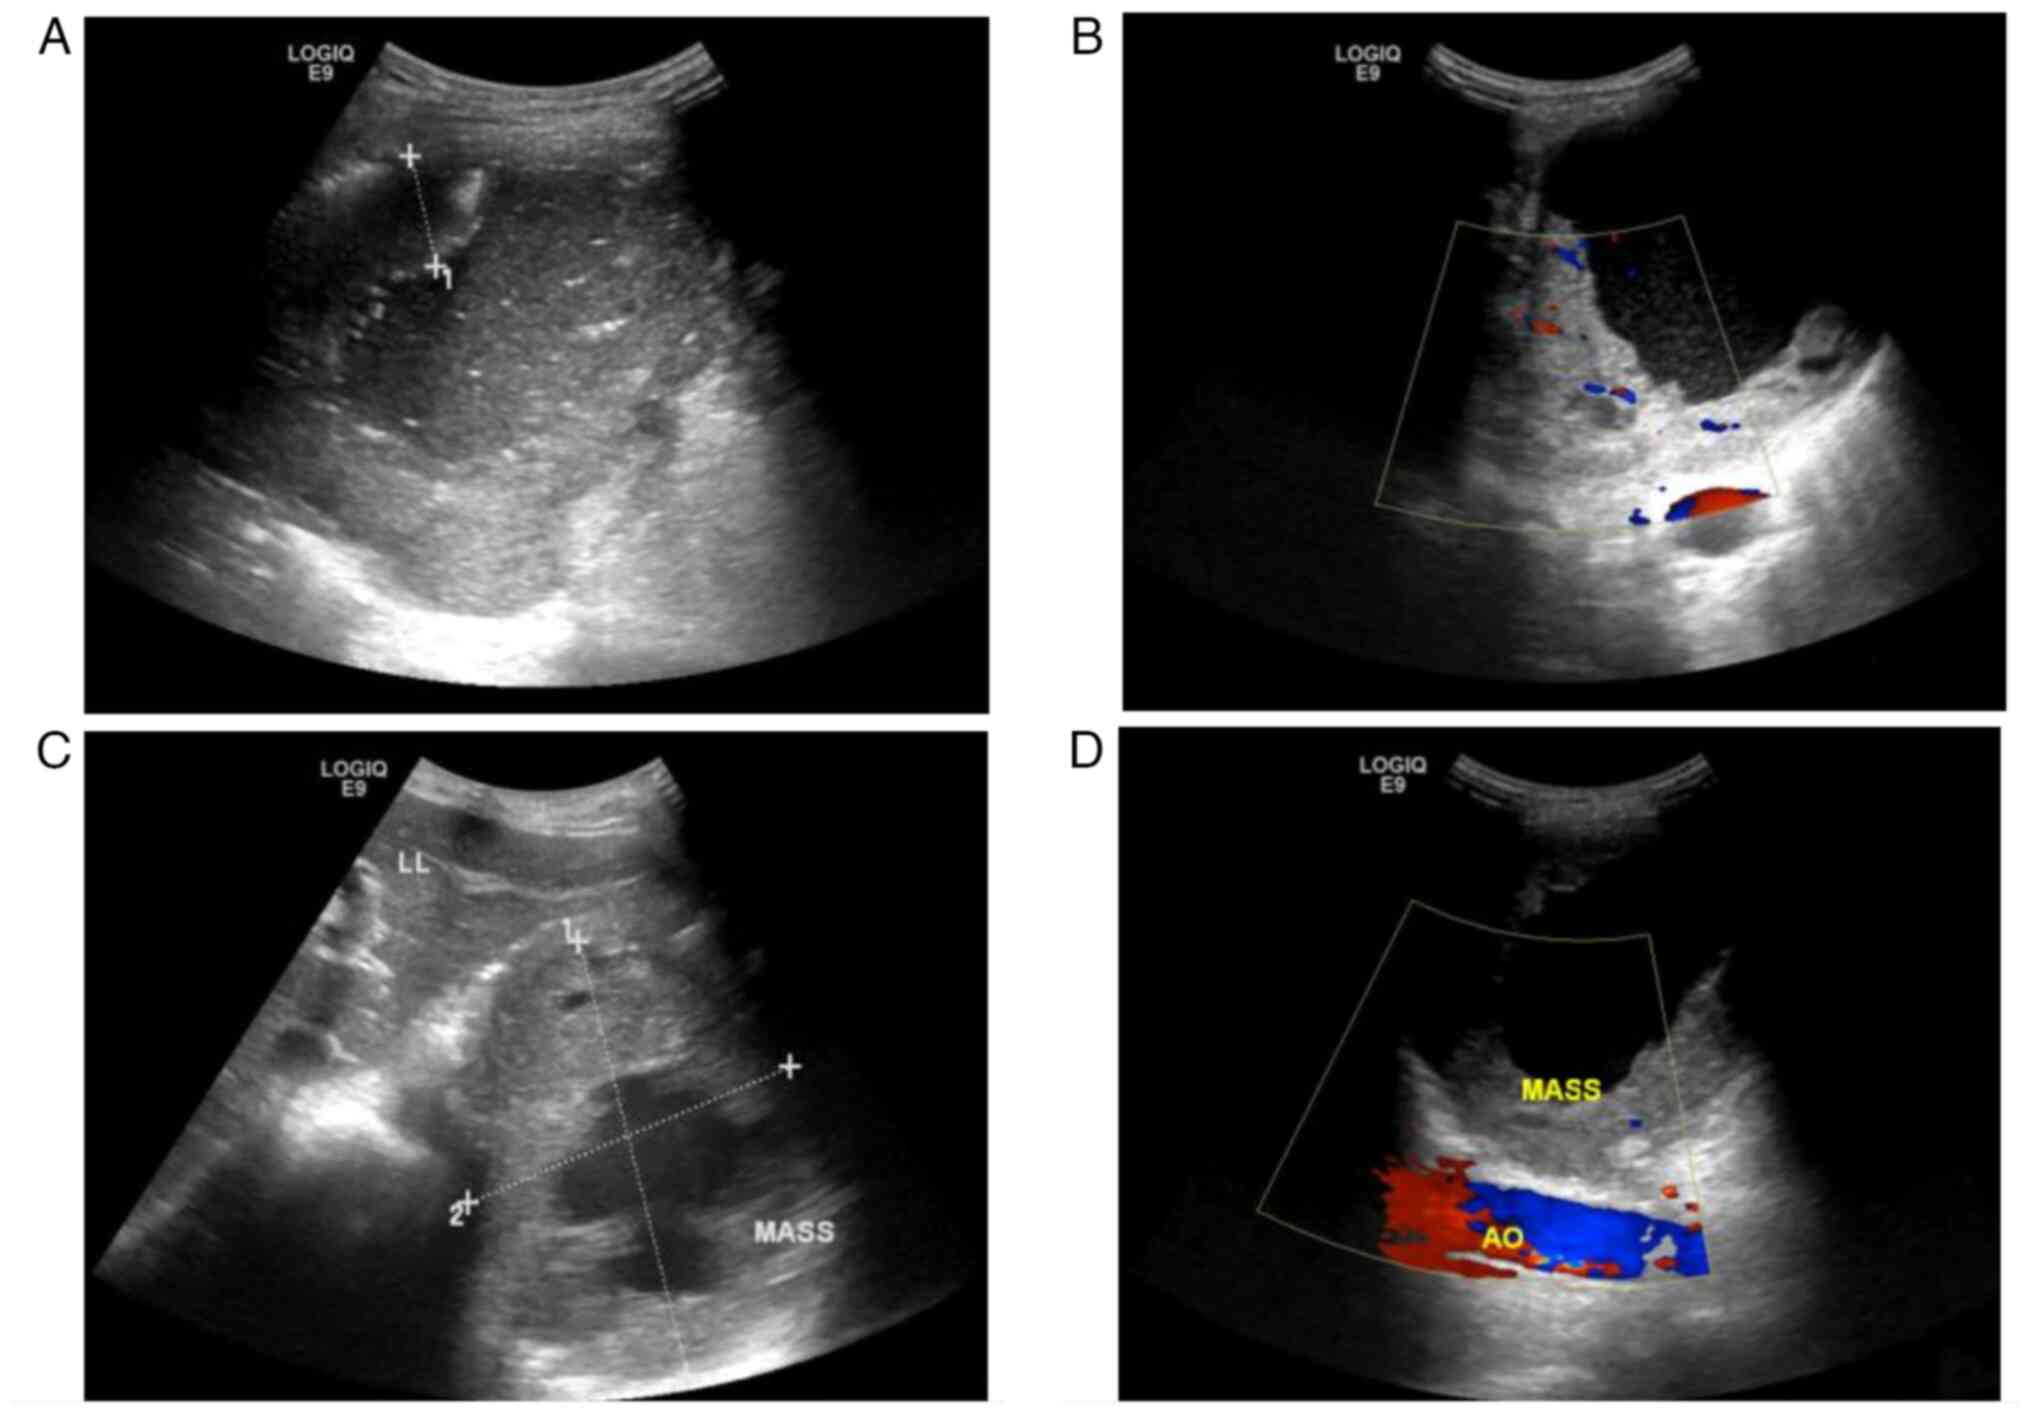

The patient underwent an immediate emergency ultrasound (US) examination (Fig. 1), which detected a 116×91-mm cystic and solid mixed-echo mass in the residual spleen under the left diaphragm. The mass was surrounded by a 22.5-mm thick hypoechoic rough wall (Fig. 1A). Blood flow was detected in the surrounding wall (Fig. 1B). An ultrasonic median longitudinal abdominal scan found that the mass was close to the left lobe of the liver (Fig. 1C), and a xiphoid downward oblique scan found that it was positioned anterior to the abdominal aorta (Fig. 1D). The patient was initially diagnosed with a splenic abscess and treated with anti-inflammatory therapy (cefotaxime 2.00 g diluted in 100 ml 0.9% sodium chloride injection, intravenous drip twice a day), but the abdominal pain was not relieved.

Figure 1.

Ultrasonographic findings. (A) Ultrasonography detected a heterogeneous echo mass in the residual spleen under the left diaphragm with thick hypoechoic peripheral wall. (B) Color Doppler ultrasonography demonstrated a blood flow signal. (C) An ultrasonic median longitudinal abdominal scan found that the mass was close to the left lateral lobe of the liver. (D) An ultrasonic xiphoid downward oblique scan found that the mass was anterior to the abdominal aorta. LL, left lateral lobe of the liver; AO, abdominal aorta.